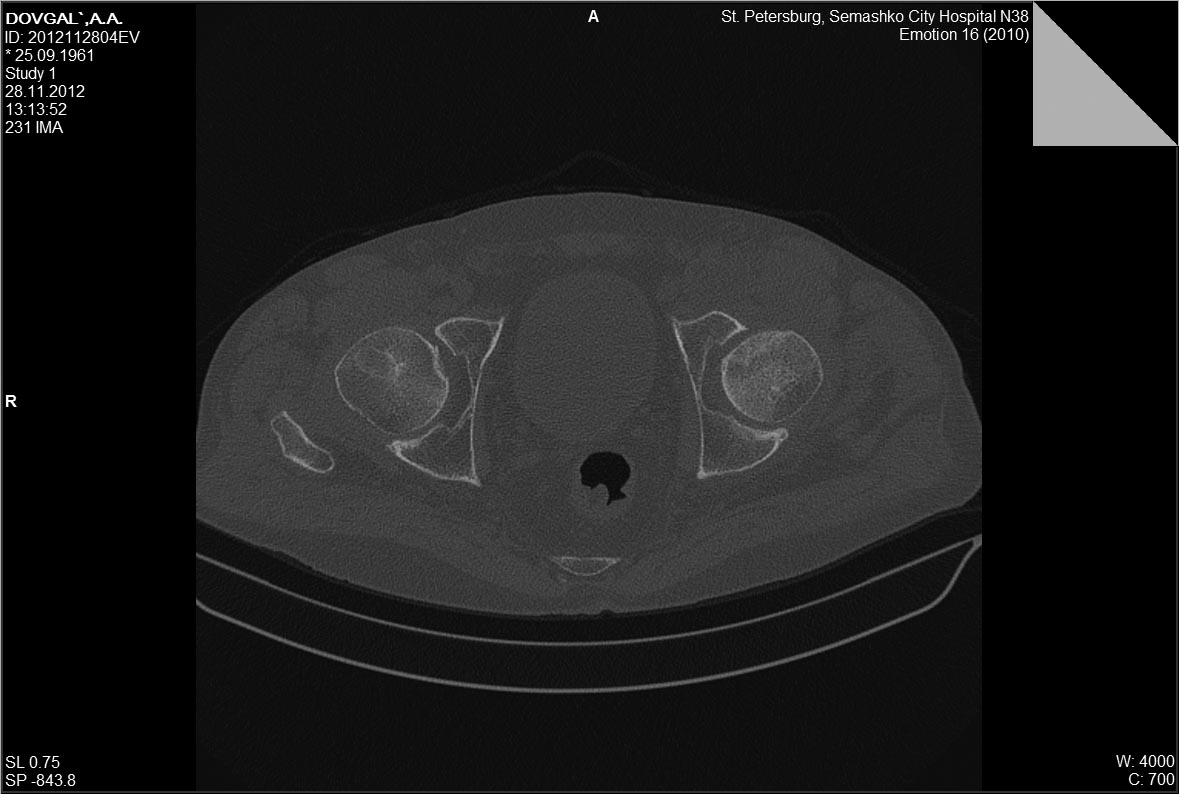

Доброго времени суток. Предлагаю к обсуждению случай с пациентом 51 года с переломом в

передне-верхней зоне головки бедренной кости. С2.2

Мужчина, 51, направлен из травмпункта в наше ЛПУ с диагнозом " ушиб левого тазобедренного

сустава". Со слов пострадавшего - 2 недели до поступления поскользнулся,упал с упором на

левое колено. После чего появились боли в области левого тазобдренного сустава, боль при

ходьбе, хромота, боль по передней поверхности тазобедренного сустава и в паху, боль

усиливалась при осевой нагрузке, беспокоила в положении на спине, и на пострадавшем боку.

Боль купировалась при сгибании в тазобедренном и коленном суставе в положении на спине. На

стандартных рентгенограммах тазобедренного сустава патологии не

выявлено.Госпитализирован в отделение с подозоением на импрессионный перелом головки

бедренной кости Выполена компьютерная томография левого тазобедренного сустава,

выявлено повреждение головки бедренной кости со вдавлением по передне-верхеней

поверхности. На данный момент больному рекомендована разгрузка, ходьба без опоры на